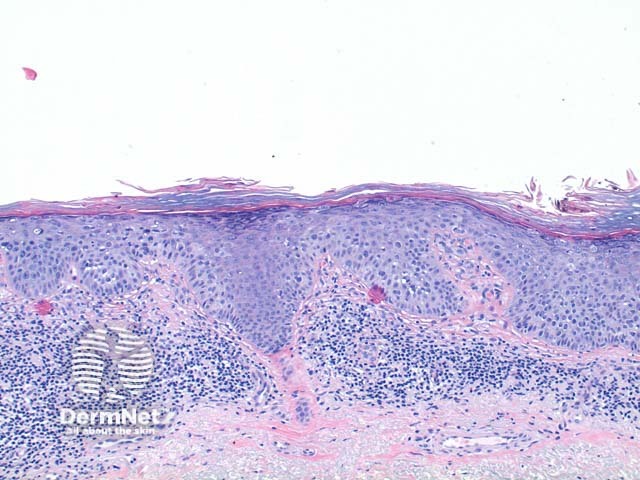

The scanning power view of squamous cell carcinoma in situ (SCCIS) reveals epidermal alteration (Figure 1). Closer inspection reveals atypia of the keratinocytes across the full thickness of the epidermis (Figures 2 and 3). There is a loss of the granular layer and overlying zones of parakeratosis. Sparing of the adnexal ostial epithelium is commonly seen (Figure 3). The keratinocytes show cytologic atypia with disorderly maturation.

Figure 2

Figure 3